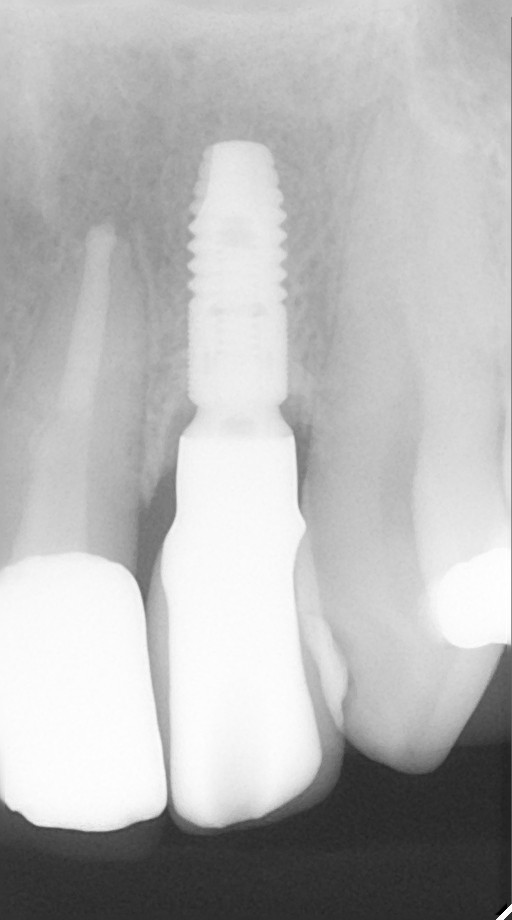

インプラント治療の症例紹介②

Before

After

主訴

前歯の脱落、歯肉の腫れ

治療内容

修復物の脱落時に支台築造のポスト部で歯質を破折。抜歯即時インプラント埋入をおこなったケース。

治療費

473,000 円(税込)

治療期間

8か月

治療回数

12回

想定されたリスク

※経年的な歯肉退縮の恐れ、インプラント周囲炎の恐れがありました。

残存した歯根に感染が少なく、抜歯時即時にインプラント埋入手術を行った。術後〇年経過し安定している状態。